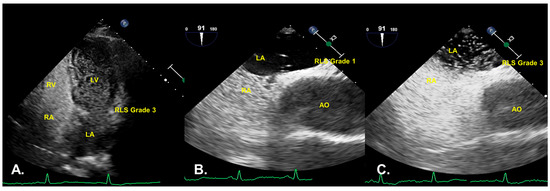

3.2. Semiquantitative Shunt Grading

| State | Right-to-Left Shunt | |||

|---|---|---|---|---|

| Grade 0 | Grade 1 | Grade 2 | Grade 3 | |

| AVM cTTE | 124 (55.3%) | 10 (4.5%) | 23 (10.3%) | 67 (29.9%) |

| non-AVM cTEE | 138 (61.6%) | 57 (25.5%) | 24 (10.7%) | 5 (2.2%) |

| AVM cTEE | 116 (51.8%) | 16 (7.1%) | 36 (16.1%) | 56 (25.0%) |